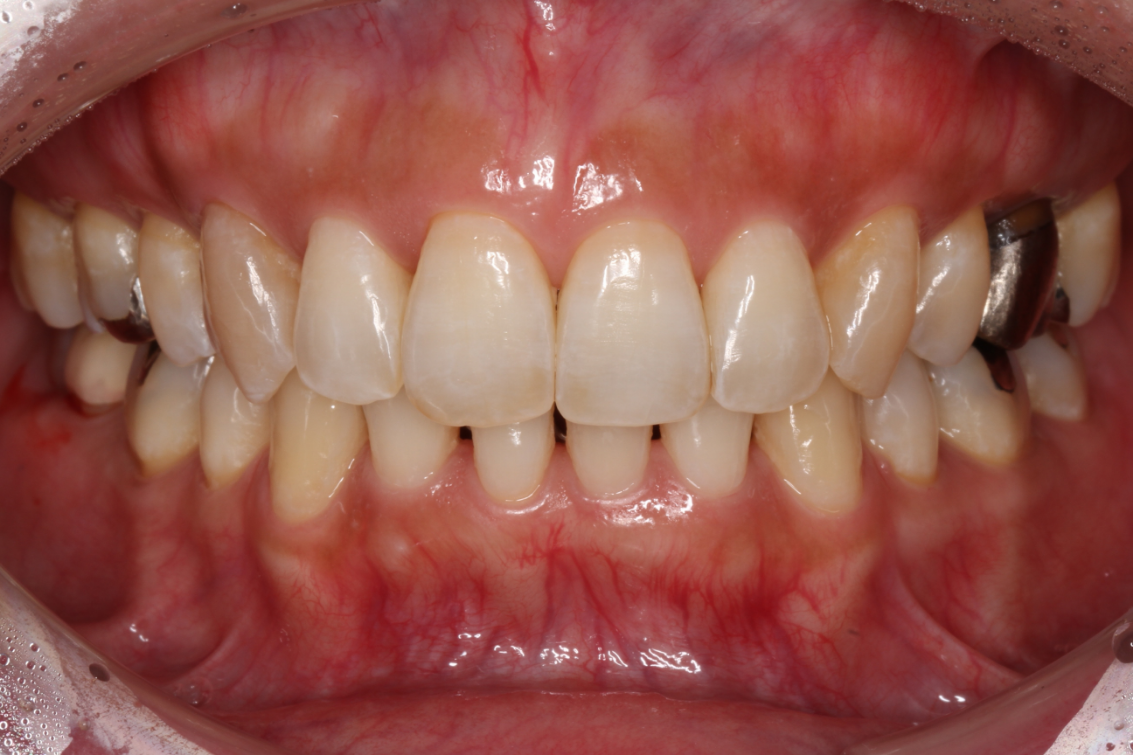

- 患者様情報30代 女性

- 来院動機歯並びが気になる

- 治療内容矯正治療

- 治療期間1年5ヶ月

- 治療費用1,063,700円(税込)

検査費、治療費、月々の調整費込 - 治療のリスク歯肉退縮の可能性がある、装置装着の痛みを感じる場合がある